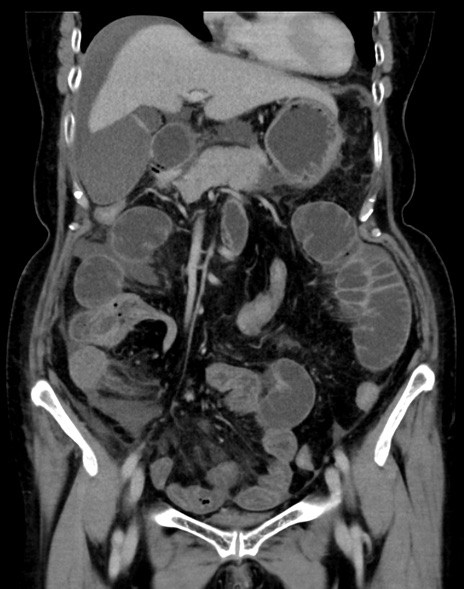

症例13 CT(冠状断像)1日半後